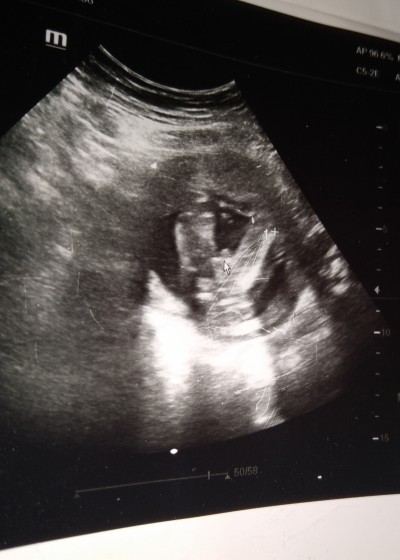

24 Mayıs 2021 Hamilelik Dönemi Genel kategorisinde (15 puan) sordu

Gebelik haftası 31 hafta

Erkek benimkide çıktı böle resim doktor erkek dedi

Hahah :)) yiğidim benim pipi gibi canım benimkide erkek çıkıntı karşıya bakarsa erkek aşağıya bakarsa kız oluyormus

Bence de erkek benim oğlumun da böyle çıkmıştı:)

Erkek canım benimde öyle çıkmıştı sağlıkla kucağına al

Bende oğluma hamileyken aynı böyleydi ultrosan kağıdı

Cnm erkek tabiki bnm ki kız böle cıkıntı yoktu düzdü doktor kızın olck dedi 32+0

Daha cinsiyeti öğrenmediniz mi ben 18 hafta da aynı boyle gordum pipi dedi dr bu da pipi benim oglan tam açtı gösterdi erkeyim  dedi  resmen :))

Hey maşallah asĺanıma.evet bendede böyle görundü erkek dedi muhtemelen